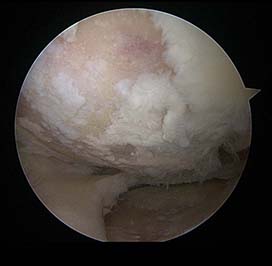

대퇴내과의 관절 연골이 파괴되어 들떠있는 모습.

관절경하에 관절경 기구를 이용하여 뼈에서 들떠있는 연골을 제거한 후 모습.